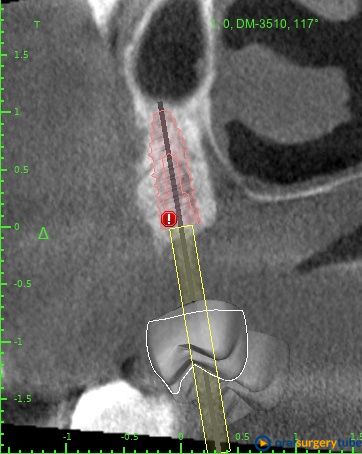

Mi plan A sería: Jugando con la cirugía guiada me cabría un implante mesial de 4x8,5 y uno pterigoideo de 3,5x10, éste en hueso nativo 100% pero con la anatomía justita. Tengo dudas si jugar en ambos lechos usar las fresas Versha para ganar algo más de altura en el mesial y mejor condensación del lecho en ambos... O no liarla y dejarlo así como os digo sin versha.